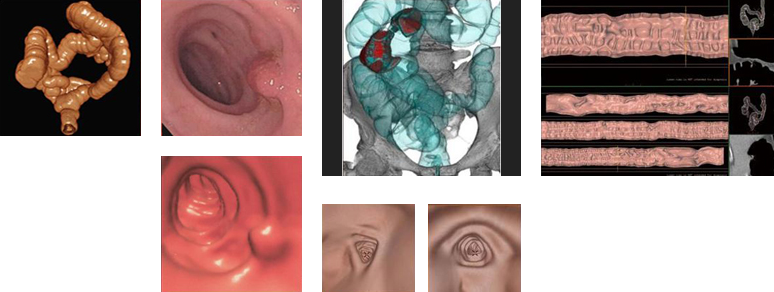

MRI検査

MRIとは、磁気共鳴断層画像診断装置(MagneticResonanceImaging)の略です。

X線検査やCT検査のようにX線を使わず、強力な磁石を埋め込んだトンネルの中に入り、電波を身体に当てることで体内の状態を断面像として撮影する事ができます。種々の撮像法の実用化により、コントラストのよい高精細な画像を比較的短時間に提供できるようになり、特に、脳・脊椎・四肢・骨盤腔(子宮、卵巣、前立腺)の病変に関しては、優れた検出能力を持っています。

CTとMRIの違い

CTはX線を、MRIは磁気を使って検査します。

それぞれ特徴がありどちらの検査を行うかは目的によって医師が選択します。